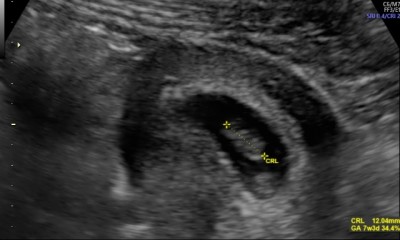

7+3 haftalık görüntüsü ramzi teorisini bilenler yorumlayabilir mi

Hayırlı olsun bebisiniz benimkiyle pozisyonu aynı bende 7 artı 3 üm erkek diye biliyorum

Bebegin kesedeki pozisyonuna göre cinsiyet belirleme teorisi